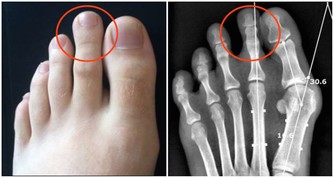

2.吃完雞蛋後不要立即吃柿子

吃完雞蛋後吃柿子輕則會得食物中毒,總則會導致急性腸胃炎還有肺結石。一般而言,這兩種食物同時吃會導致以上吐、下瀉、腹痛為主的急性胃腸炎癥狀。所以如果服用時間在1~2小時內,可使用催吐的方法。立即取食鹽20g加開水200ml溶化,冷卻後一次喝下,如果不吐,可多喝幾次,迅速促進嘔吐。或者可用鮮生薑搗碎取汁用溫水沖服。如果服用時間較長,儘快服用些瀉藥將有毒物質排除體內。